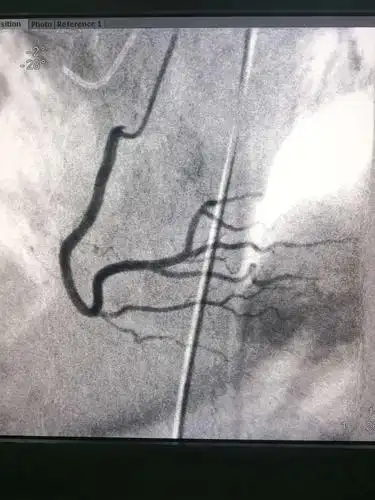

永昌县医院首次成功完成5例心脏冠状动脉造影检查术

有图有真相,大家关心的急诊冠状动脉造影和介入治疗来啦!

小心植入动脉鞘管,可以正常造影啦!

全市首例罕见"右位心"冠状动脉造影术在山阴县医疗集团人民医院成功

心脏冠状动脉造影手术正在进行

为"心"插上翅膀,汉阴县人民医院成功开展"冠状动脉造影术"

虎口连心—记第一次远桡穿刺冠脉造影术